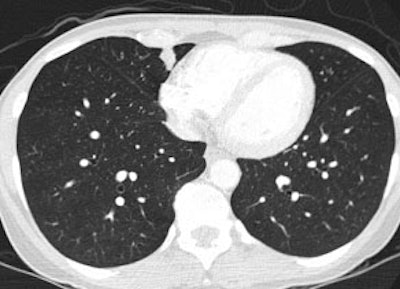

Bronchoalveolar cell carcinoma (BAC): The images below were from a patient with bronchoalveolar cell carcinoma that presented as a chronic right lung infiltrate. The FDG PET exam was positive in this case despite a higher likelihood of a false negative exams in patients with BAC. Note the most intense area of FDG accumulation corresponds to the area of greatest consolidation on CT imaging. |

|